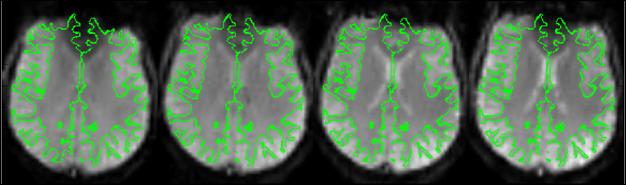

The same subject scanned on four different scanners using the FBIRN methods (2009). Green lines indicate the grey/white matter boundary from a co-registered T1 scan.